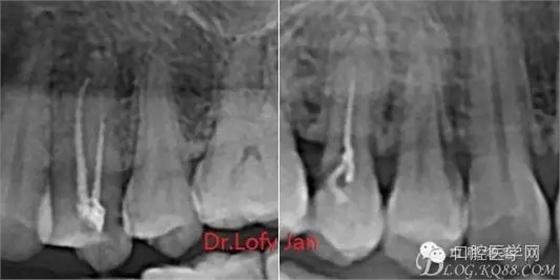

曲面斷層片在未試尖根管治療中的病例整理

前言:自己做的一些曲面斷層片在未試尖根管治療中的病例整理,發(fā)現(xiàn)問題很多包括自身的,技術(shù)的,還有設(shè)備的問題,予以總結(jié)整理并期待進(jìn)一步提高。

病例分析:曲面斷層片在x線輔助診斷與檢查中目前大多數(shù)文獻(xiàn)和著作都建議只能作為初診拍片檢查手段,不能作為終末疾病的確診與手術(shù)療效的評(píng)價(jià)指標(biāo),臨床大部分中小型門診都因?yàn)樵O(shè)備不齊全導(dǎo)致信息偏差很大。